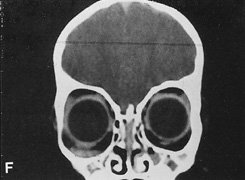

Fig. 16. A. Patient with right orbital cellulitis. B. Coronal CT scan demonstrating subperiosteal abscess formation from frontal and ethmoidal sinusitis. C. Frontoethmoidal orbitotomy incision marked for abscess drainage.